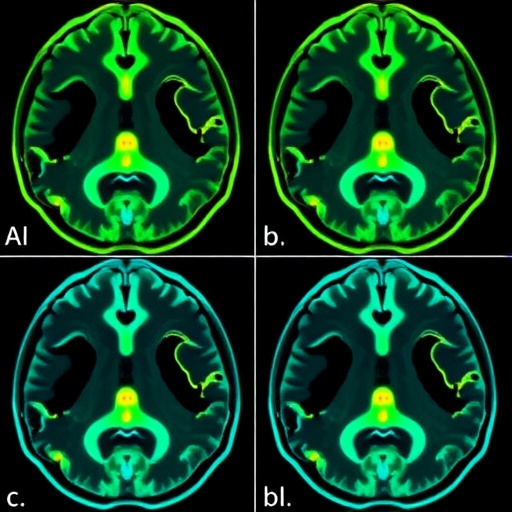

In the context of this research, the researchers assembled a cohort of radiologists and clinicians to evaluate preoperative imaging findings from a defined set of patients diagnosed with posterior fossa tumors. Each observer was tasked with assessing specific imaging biomarkers that prior studies had correlated with the incidence of CMS, including morphological and functional changes in brain structures noted on MRI. The insights gained from this multiobserver pilot study are expected not only to benefit imaging protocols but also to enhance overall multidisciplinary approaches in the management of conditions surrounding posterior fossa tumors.

The researchers documented variation in interpretations across multiple observers, revealing significant discrepancies in how imaging biomarkers were assessed. This interobserver variability poses a challenge, as it complicates the establishment of standardized diagnostic criteria necessary for effective management of CMS. The implications of these findings are profound, as they underscore the need for further training and calibration among radiologists and clinicians who interpret neuroimaging in pediatric populations.

Moreover, the study emphasized the quantitative assessment metrics required to analyze the reliability of observer assessments. By employing statistical measures such as Cohen’s kappa coefficient, the researchers could determine the degree of agreement among observers regarding the presence or absence of specific biomarkers. This rigorous evaluation served to illuminate areas where consensus was achieved and where significant variations existed, informing future refinements in imaging protocol development.